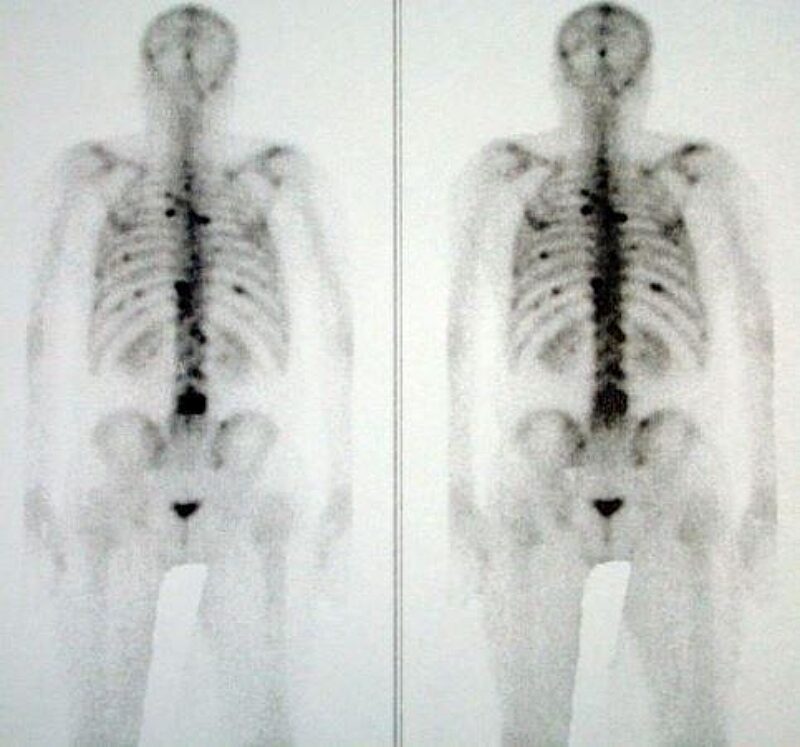

Остеосцинтиграфия

Наиболее информативный метод выявления метастазов в костях. Радиоизотопное сканирование костей может быть рекомендовано всем пациентам с дифференцировкой опухоли по Глисону ≥ 8 или ПСА превышающим 10.